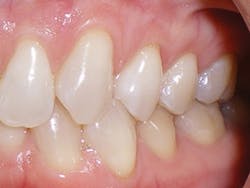

Dr. Miraglia: Victoria's long-term history and recovery

Victoria was similar to Sandra, but had more advanced deterioration. Victoria had a history of recession and abfraction as well as composite resin restorations placed to restore the abfracted areas. Victoria also had her malocclusion for a longer period of time, so she has had the opportunity to have restorations and the continuation of the recession and further abfraction areas occurring around the existing buccal composites (see Figure 4). Eventually, this led to the buccal composites falling out, which is evident in the photos. This process of recession, abfraction, composite filling, more recession and abfraction, and another composite filling, etc. happens for a reason. When we place composites, we are treating the symptoms and not the cause of the abfractions.

Figure 4

Victoria validated this by describing that she had been going to the dentist routinely, always needing something repaired. In Victoria's case, as with many others, the cause was the malocclusion; the indicated treatment was to develop the arch form and width, and to level and align the teeth to deliver a better, protective occlusion.

After taking a full set of records, Victoria's consultation involved using her photographs to teach the extent of the deterioration her malocclusion had caused. We discussed recession, bone loss, periodontal probing depths, abfractions, gingivitis, decay, fractured cusps, worn enamel, failed restorations, and continued deterioration. We taught the difference between a good bite and a bad bite and discussed the opportunities to treat the cause of the deterioration with clear aligners first and then perform the restorative dentistry second.

Victoria agreed to our recommendation. Clear aligner therapy was accomplished with 25 aligners, which took 12 months. Then, full-coverage esthetic restorations were placed on teeth Nos. 3-14 and also teeth Nos. 19 and 20. A lower lingual bar was bonded to all six lower anterior teeth, Nos. 22-27.

Correcting the malocclusion directly contributed to the improvement in the health of the gum tissue. The restorative dentistry was accomplished easily thanks to the gum tissue being pink, healthy, and tight, with shallow pockets. After completing the comprehensive care treatment for Victoria, she was placed on a four-month recall that she continues to maintain. Five uneventful years have passed, and the five-year follow-up photos show stability and health. Victoria enjoys all of the function and strength from her good bite and dental restorations without any deterioration at the five-year mark. The key to periodontal health and restorative success and stability is the correction of the malocclusion. The clear aligner therapy was the cornerstone of this comprehensive treatment plan.